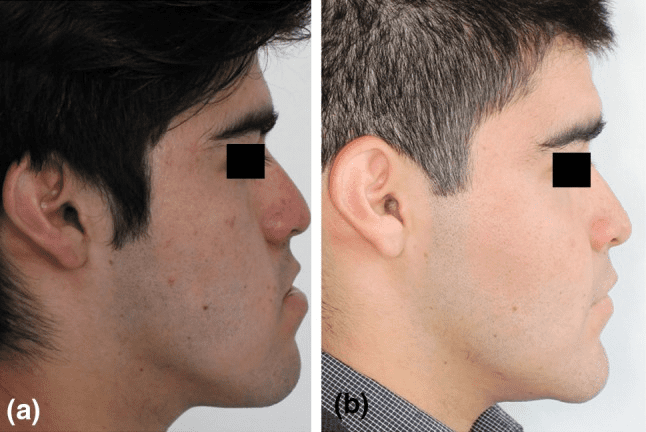

It moves cheekbones upward, give so much under eye support and even change orbital shape. Also widen face and change gonial angle. Is it modified lefort 3?